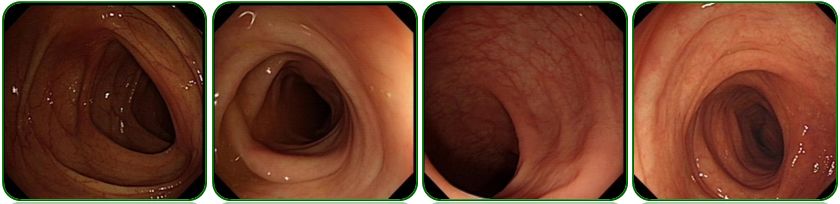

肺部及腹部CT提示右侧胸腔大量积液,右肺中下叶局限性膨胀不全、左肺上叶前段小结节影、纵隔稍肿大淋巴结、腹腔大量积液、盆腔少量积液、肝胆脾、胰腺及双肾CT平扫未见明显异常征象,如图5;

图5 胸部及腹部CT检查